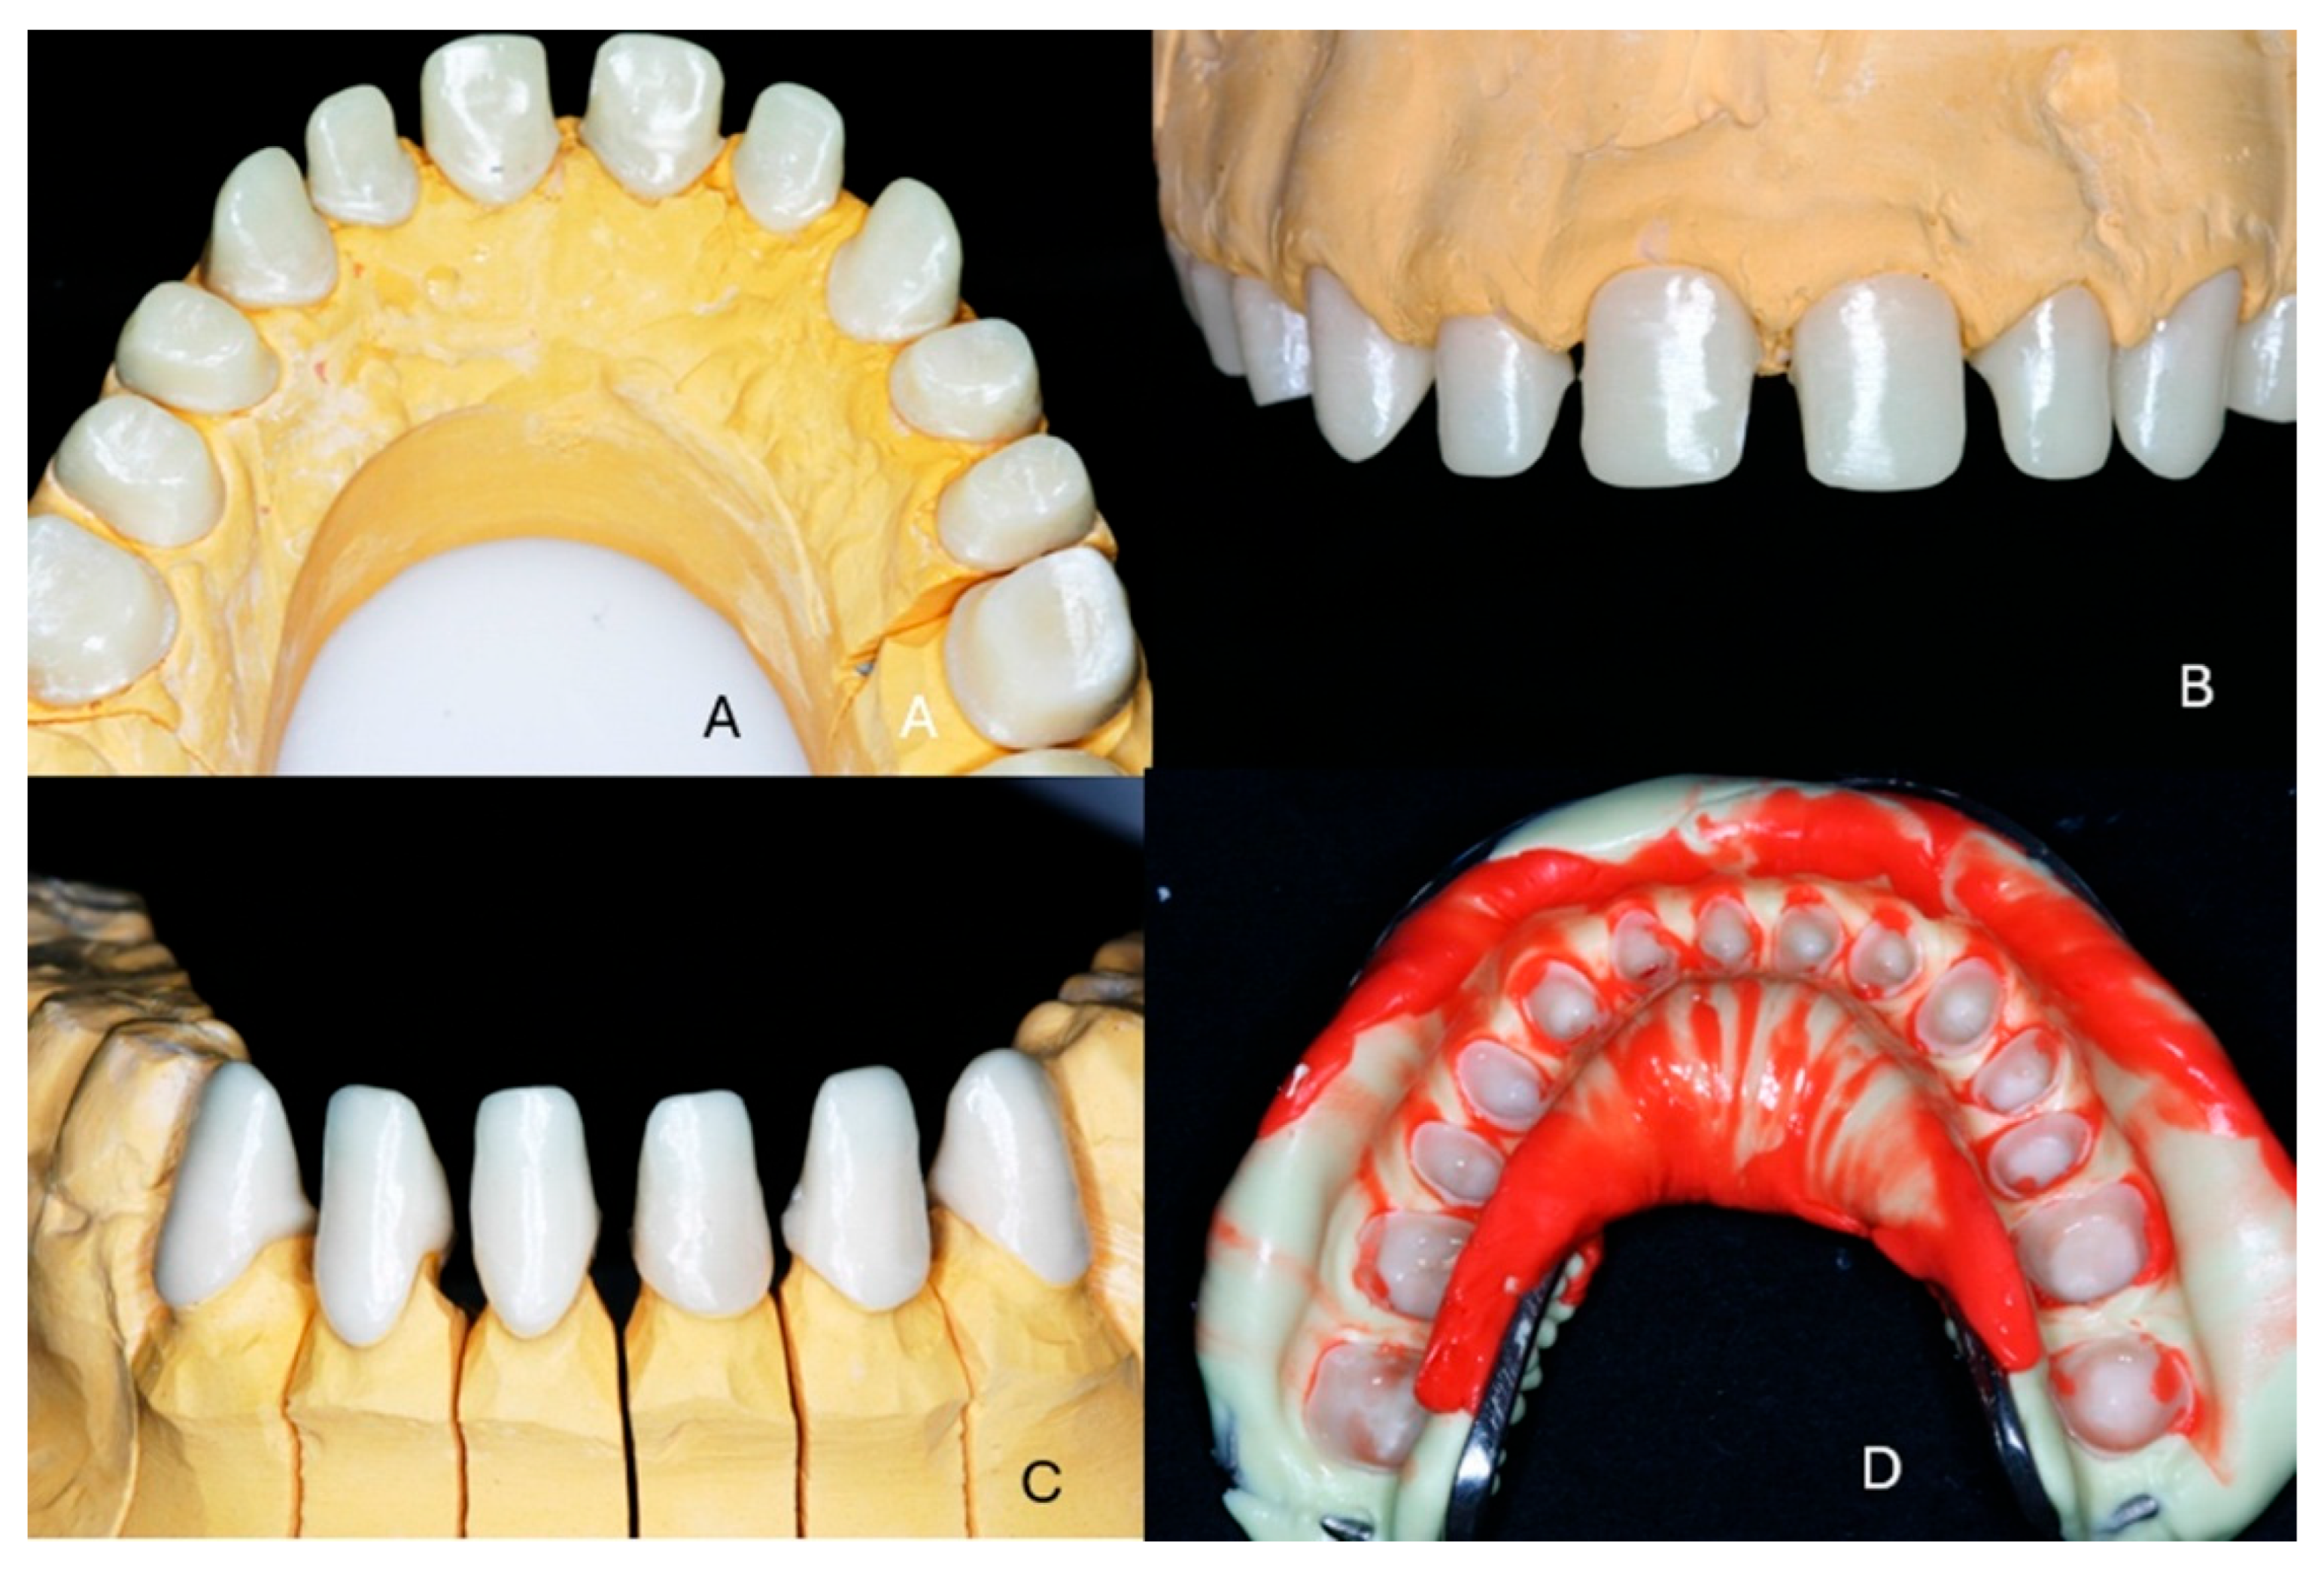

2. Case Presentation